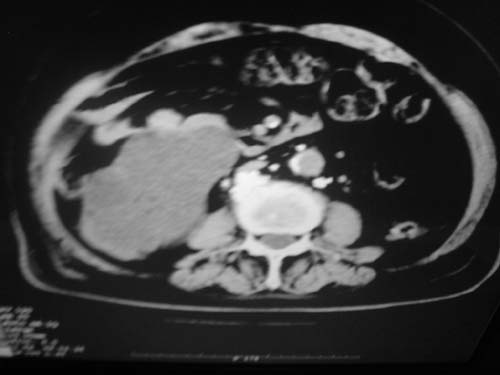

以下是引用余辉在2009-3-11 21:12:00的发言:[br]1肝脾多发钙化结节2右肾结石,右肾积水

以下是引用jiangjing在2009-3-12 17:05:00的发言:[br]1肝脾多发钙化结节2右肾结石,右肾积水 3胆囊炎[br] [br] 左肾囊肿